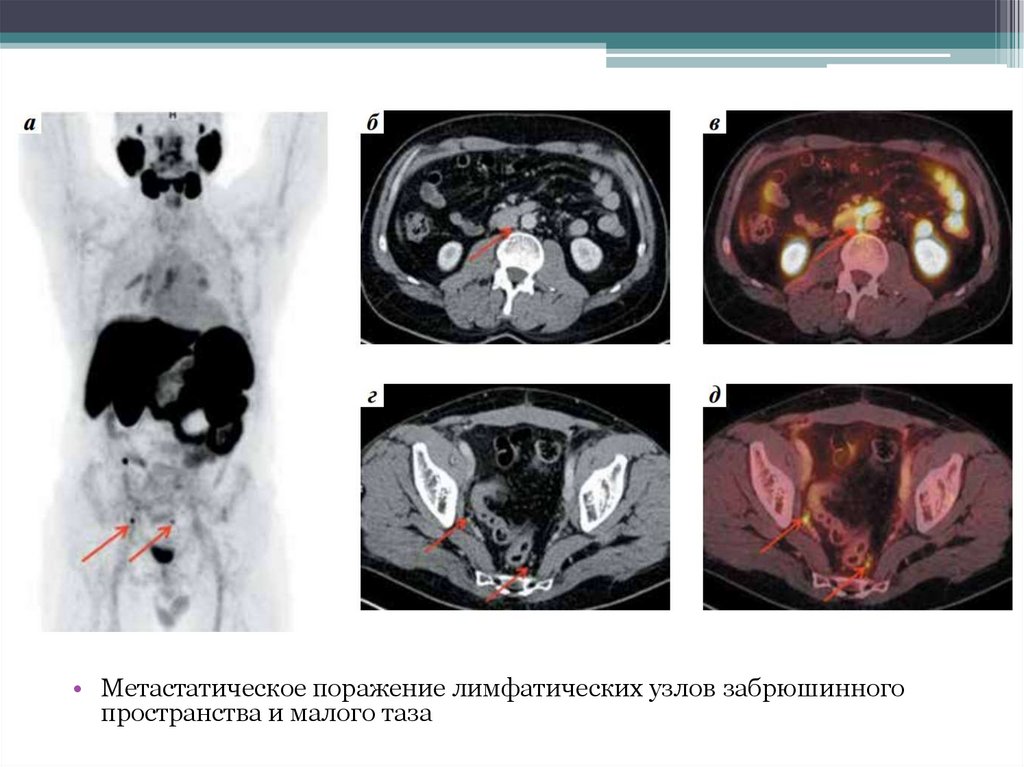

• Метастатическое поражение лимфатических узлов забрюшинного

пространства и малого таза